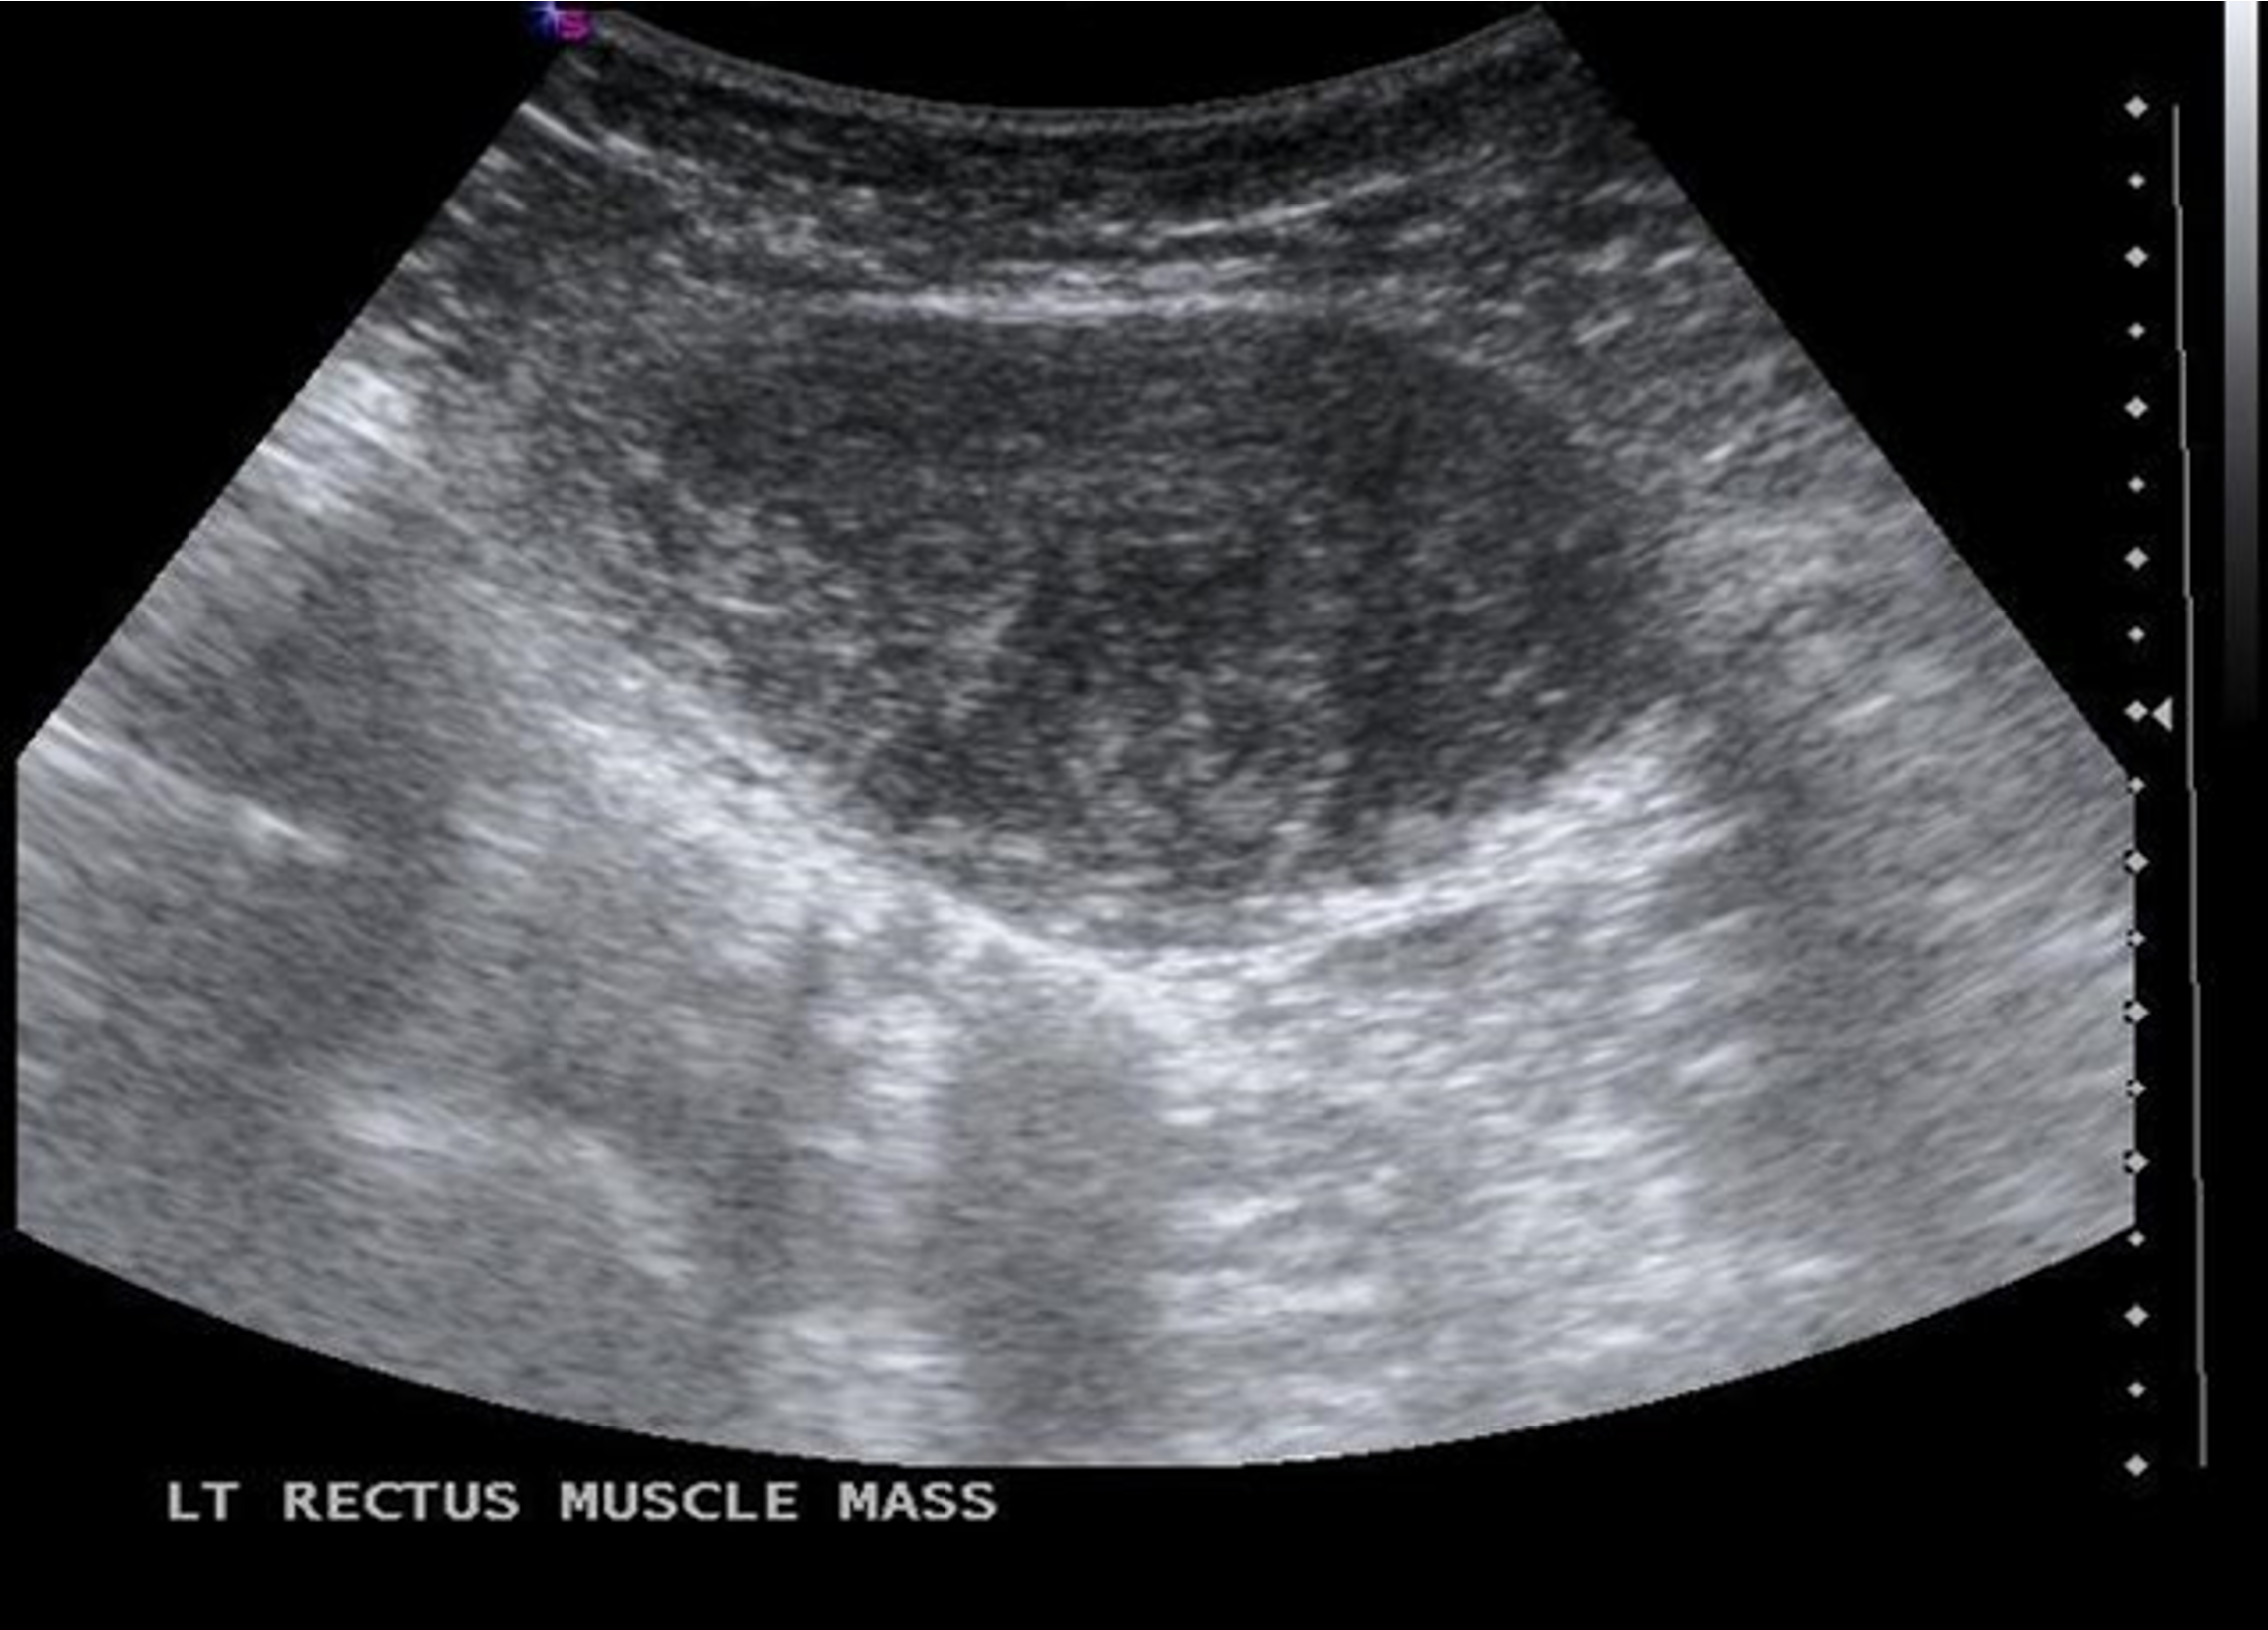

- Fibromatosis/ neoplasm: from fibroaponeurotic part of rectus abdominis.

- More common in young female of child bearing age, OC use.

- Diagnosis: CT or MRI for delineation, core needle biopsy.

- Treatment: Wide local excision. Local recurrence high if margins are involved.